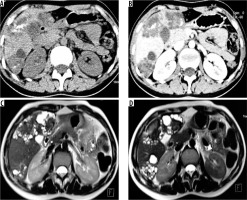

Figure 2

A) Transverse sonogram of liver shows a large heterogeneously hyperechoic mass with central foci of calcification (arrow). B) Axial non-contrast computed tomography (CT) image shows hypodense mass with central calcification (arrow). Post-contrast axial CT images (C, D) do not reveal any enhancement of the mass. There is left lobe biliary dilatation (P2 disease)

Figure 4

A) Non-contrast axial computed tomography (CT) image in a patient showing large thick-walled cystic mass in segment VII and VIII with peripheral calcification. B) Corresponding arterial phase axial CT image reveals absence of any enhancement. C) Axial non-contrast CT image in a different patient shows large heterogeneous density mass lesion in segment VII and VIII with sheet-like central calcification. D) Corresponding post-contrast axial CT image reveals no enhancement of the mass. The lesion is seen infiltrating the right and middle hepatic vein (P3 disease)